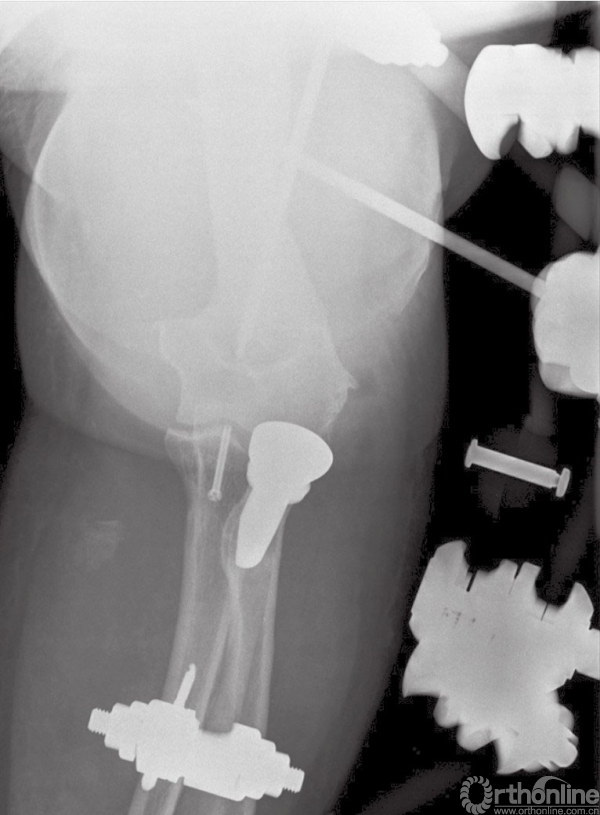

图8 (与图2为同一患者)使用铰链式外固定支具后的术后正位X线片

图9 (与图2为同一患者)使用铰链式外固定支架后的术后侧位X线片

在内固定完成和韧带的损伤修复后,在手术台上验证患者肘关节的稳定性。如果发现肘关节稳定性不可靠或者存在再次脱位风险,建议使用铰链式外固定支架,这样可以使肘关节获得同轴心的稳定性,并可以使患者在术后早期活动。

对于没有合并并发症的患者,我们也倾向于术后使用铰链式外固定支架,以避免不可控的关节活动。使用外固定支架可以中和修复后骨折端及韧带复合体所受的应力,防止术后早期活动时发生再脱位及内固定失败。外固定支架一般使用6周(图12)。

图12 术后使用铰链式外固定支架,有利于术后软组织损伤恢复及早期活动